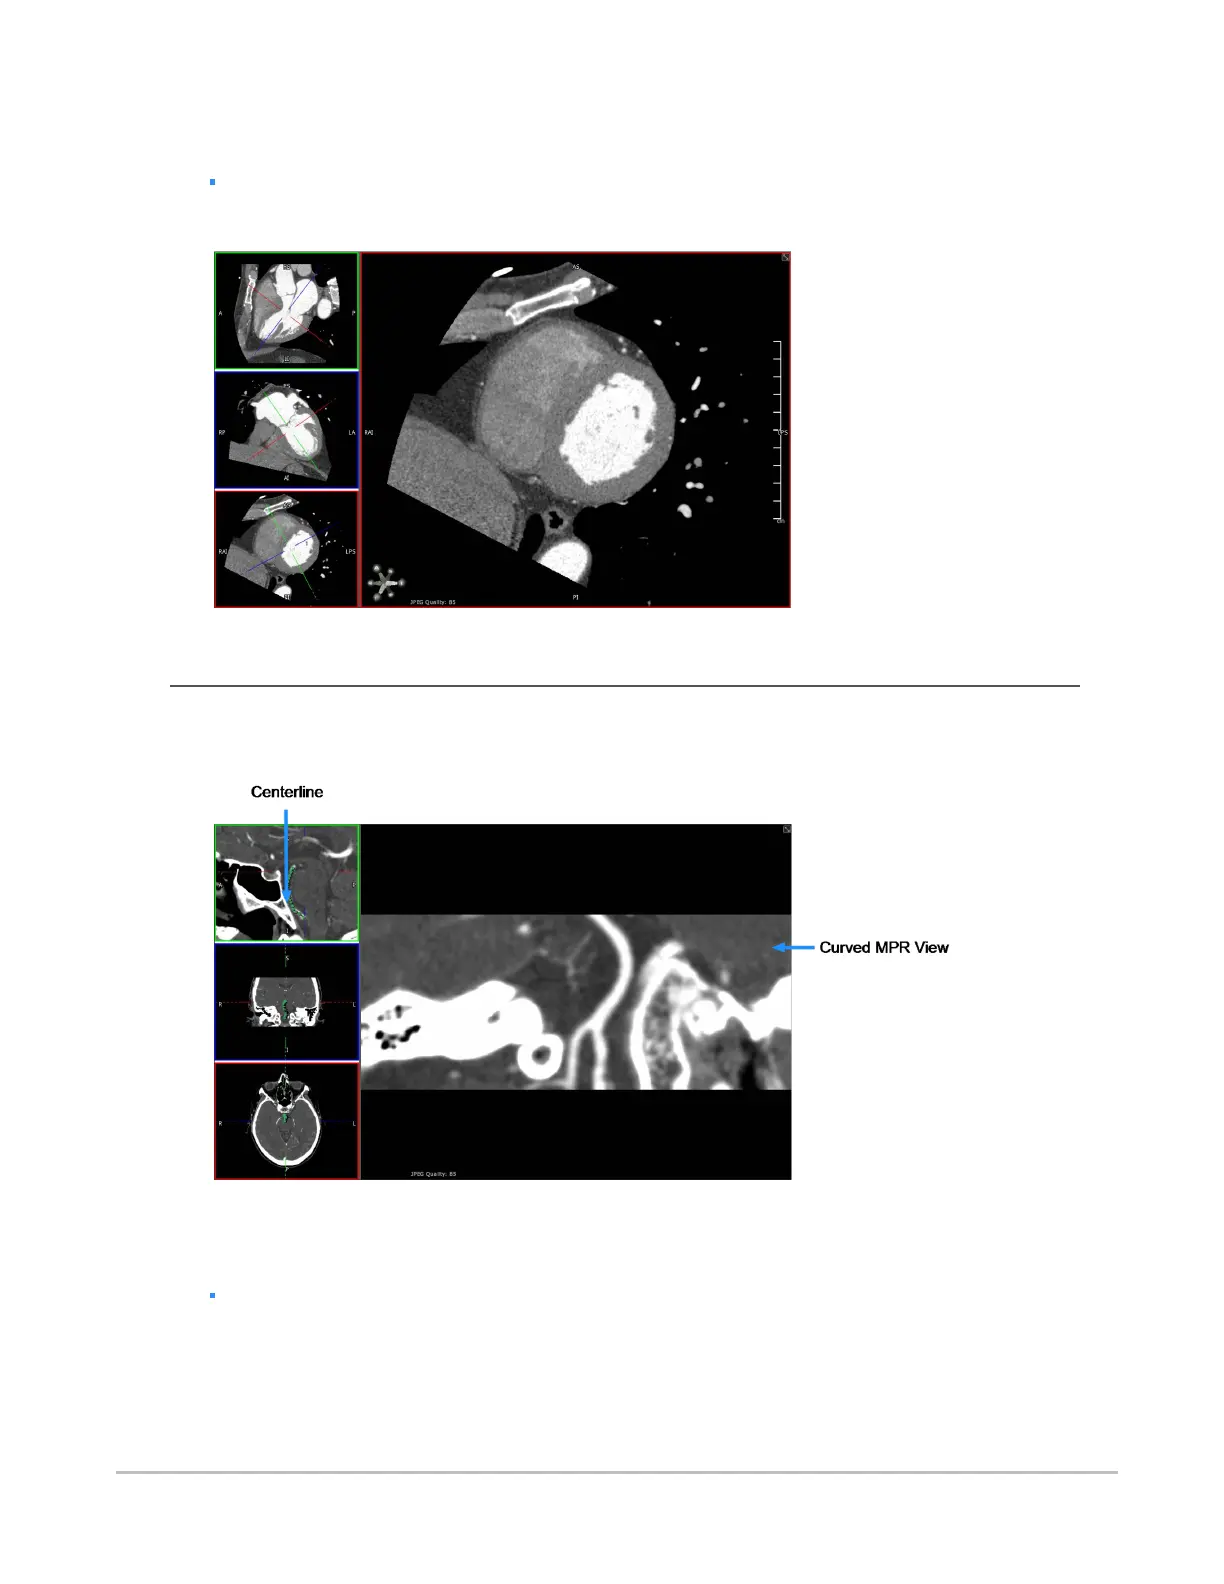

The following double oblique view was created using these methods.

Using curved MPR

You can assign the curved MPR view to the main view by double-clicking the curved MPR view, as seen in

the following example.

The following procedures describe how to use the curved MPR view.

To enable curved MPR

Select CMPR from the view menu.

By default, the bottom left pane becomes the curved MPR.